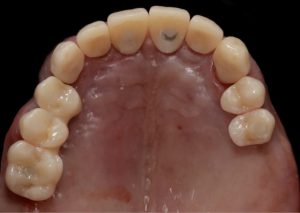

Healing abutments were removed and (b) the second set of temporary restorations was paced. Fig. 17 (i,ii)

Periapical radiographs to verify the seat of the implant- retained provisional restorations. Fig. 18

Immediate post-operative view of the inserted provisionals. Fig. 19 (i,ii)